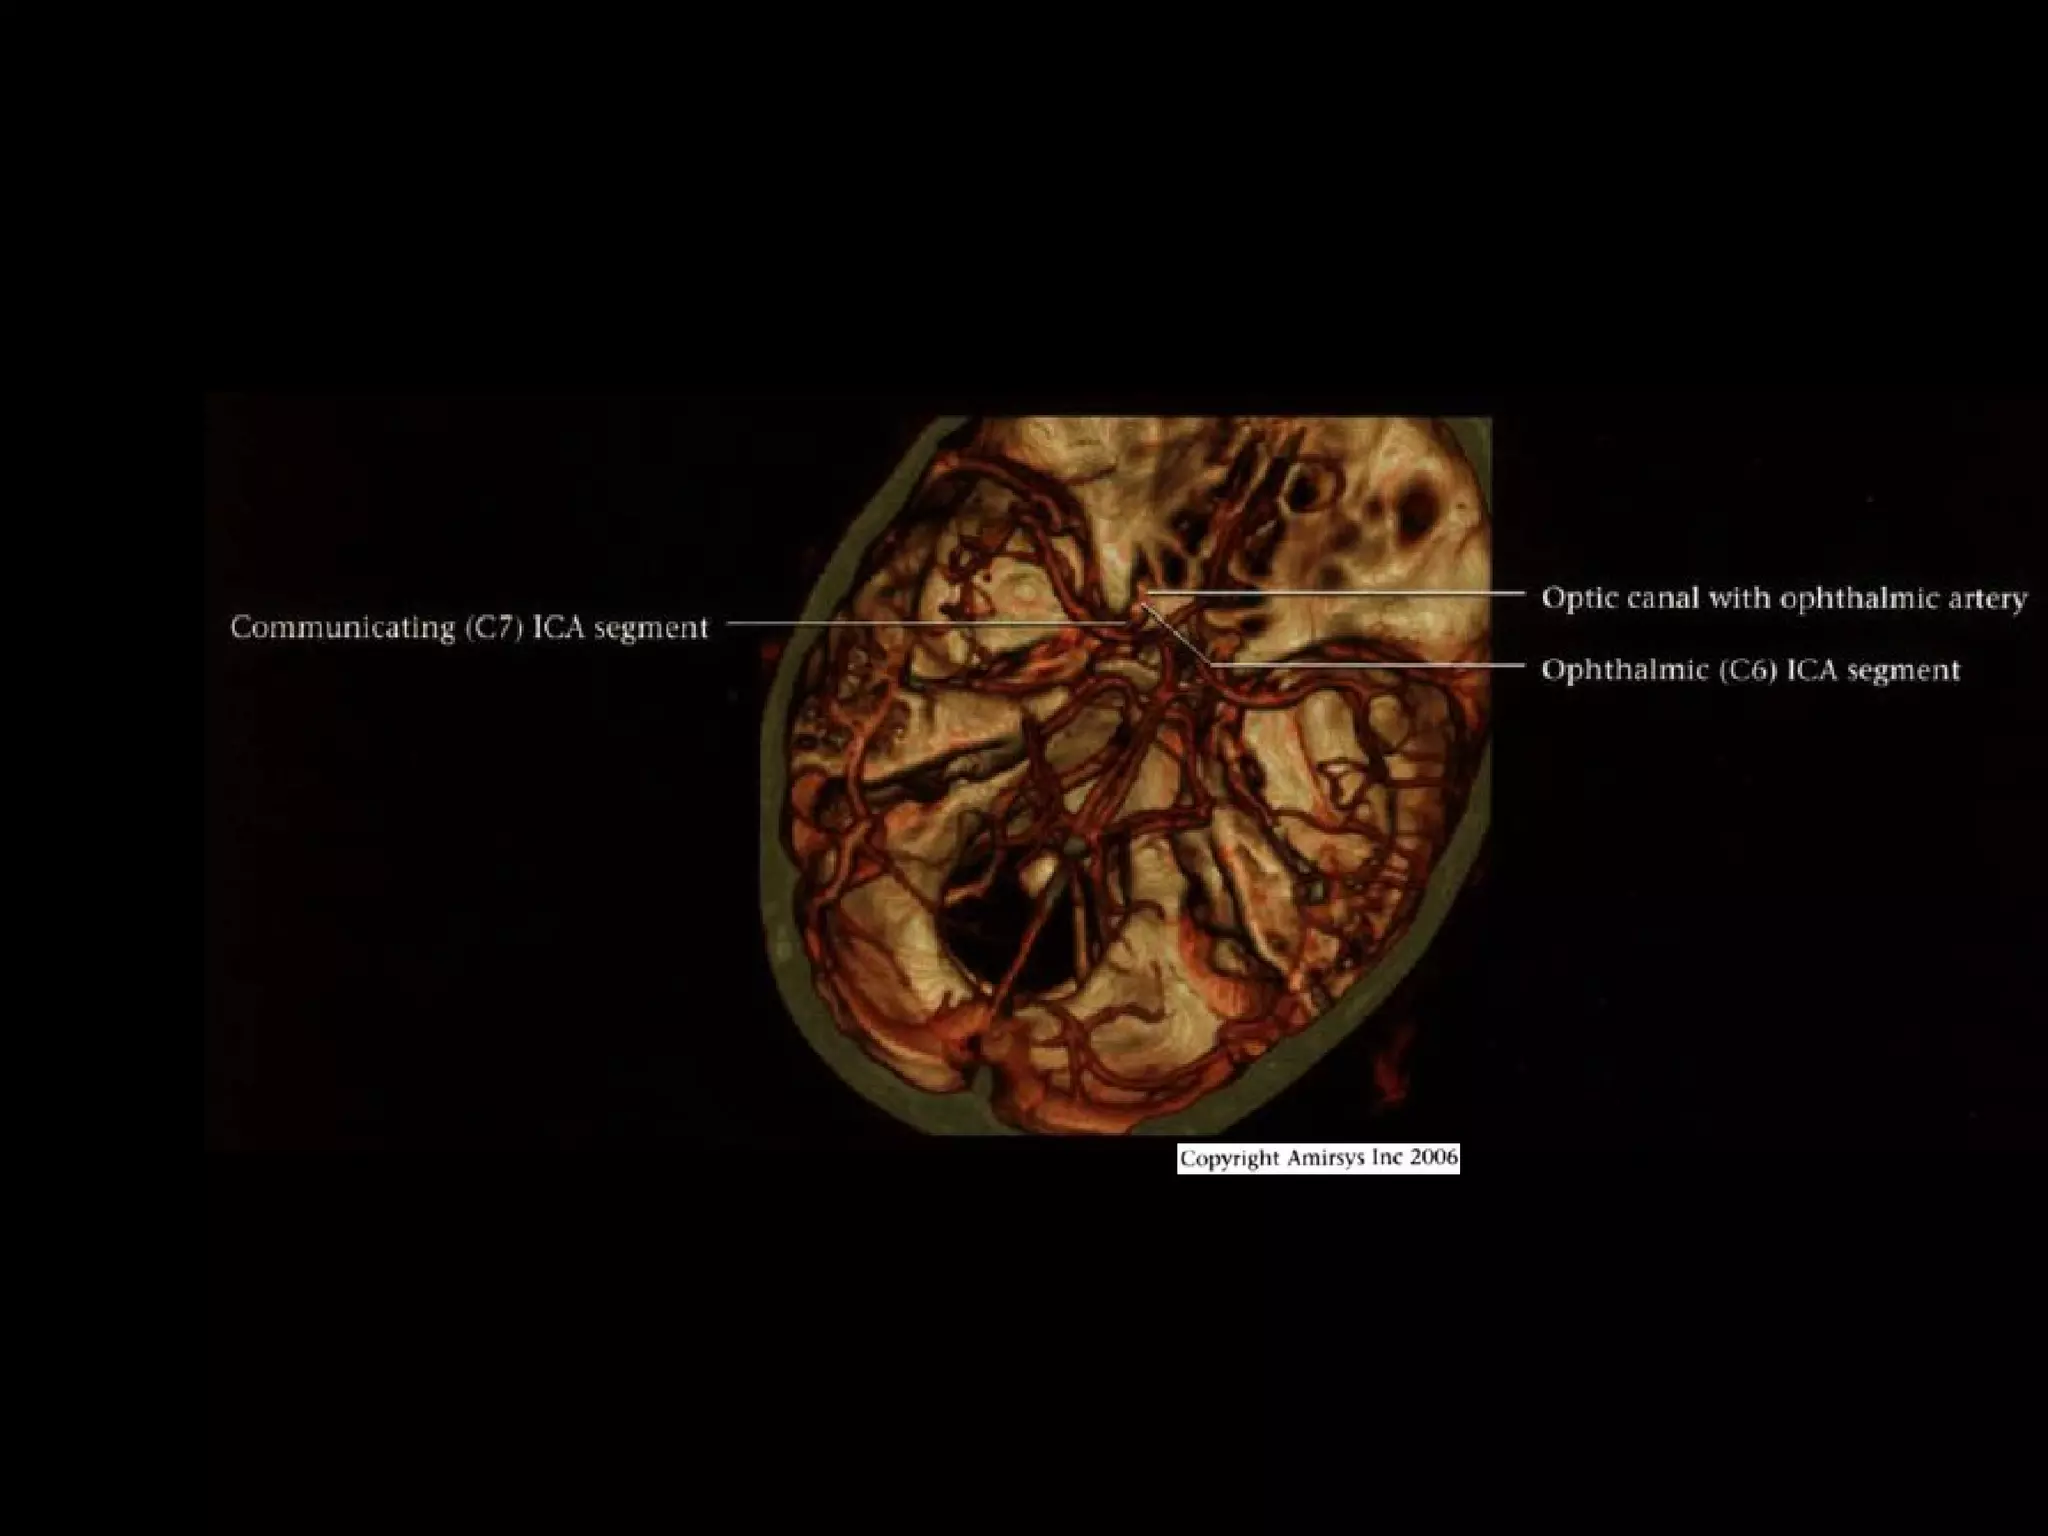

INTRACRANIAL INTERNAL

CAROTID ARTERY

Overview

• Complex course with several vertical /

horizontal segments, 3 genus (one

petrous, two cavernous)

• Six intracranial segments (Cervical lCA =

C1):

- Petrous (C2), Lacerum (C3),

Cavernous (C4), Clinoid (C5),

Ophthalmic (C6), Communicating (C7)

Ophthalmic (C6) segment

• Extends from distal dural ring at superior clinoid

to just below posterior communicating artery

(PCoA) origin

• Two important branches

- Ophthalmic Arteries (originates from

anterosuperior ICA, passes through optic canal

to orbit; gives off ocular, lacrimal, muscular

branches; extensive anastomoses with ECA)

- Superior hypophyseal artery (courses

posteromedially; supplies anterior pituitary,

infundibulum, optic nerve / chiasm)

Communicating (C7) segment

• Extends from below PCoA to terminal lCA bifurcation

into anterior cerebral artery (ACA), middle cerebral artery

(MCA)

• Passes between optic (CN2), oculomotor (CN3) nerves

• Major branches

- Posterior communicating artery

- Anterior choroidal artery (courses posteromedial,

then turns superolateral in suprasellar cistern; enters

temporal horn at choroidal fissure; supplies choroid

plexus, medial temporal lobe, basal ganglia,

posteroinferior internal capsule)